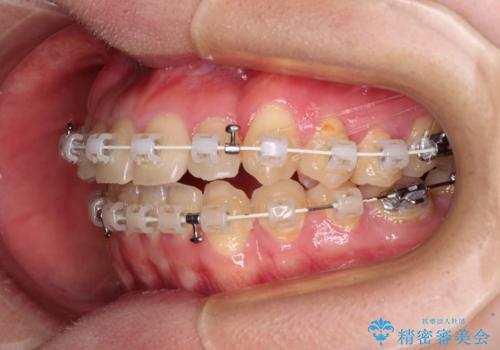

マウスピース矯正は自己管理が煩わしいとのことで、ワイヤー装置にて矯正治療を行うこととしました。

思っていた以上に上顎歯列を後方に移動させることができ、すっきりとした口元に仕上げることができました。